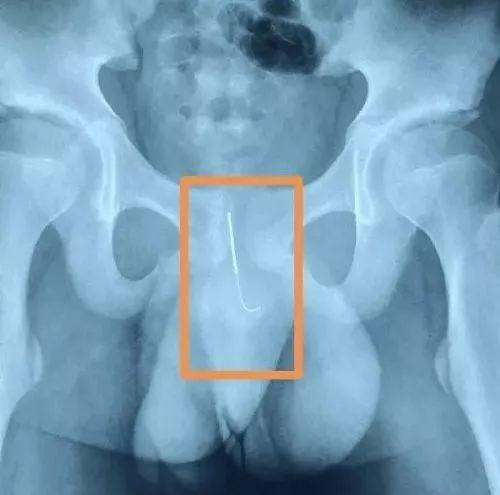

父母一听大惊失色,连忙拨打120把乐乐送往医院。还好送到的及时,医生通过手术把缝衣针从乐乐的*体下**取了出来,这艮缝衣针长达8cm,属于大号的缝衣针了,并且缝衣针表面有锈迹。虽然手术进行得比较顺利,但是乐乐的尿道还是受到了损伤,需要插尿管治疗一段时间。还好乐乐的身体并无大碍,不然后果不堪设想。即使是在家里孩子也会面临很多危险,家长一定要注意对孩子的安全教育。